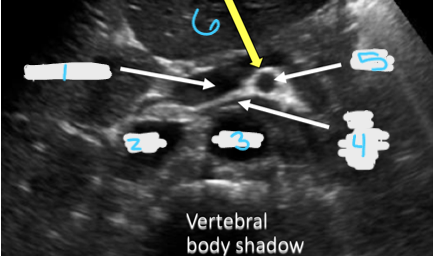

<p>In this transverse view, what is #1?</p>

In this transverse view, what is #1?

Aorta

<p>In this transverse view, what is #2?</p>

In this transverse view, what is #2?

Common Hepatic Artery

Portal Vein

IVC

<p>In this transverse view, what is #3?</p>

In this transverse view, what is #3?

<p>In this transverse view, what is #4?</p>

In this transverse view, what is #4?

Left Renal Vein

<p>In this transverse view, what is #5?</p>

In this transverse view, what is #5?

SMA

<p>In this transverse view, what is #6?</p>

In this transverse view, what is #6?

Splenic vein